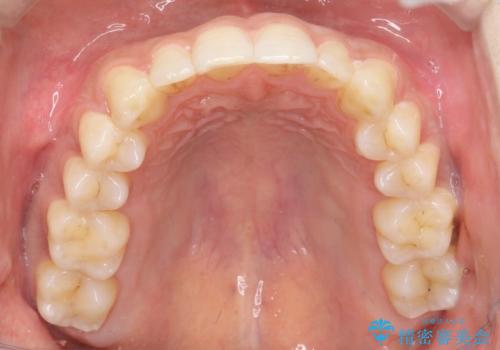

初診時の歯並びの状態としては、下顎に中等度のがたつき(叢生)がある状態でした。

抜歯は行わず下顎の奥のスペースを利用して歯をスライドする方法の他に親知らずの抜歯そして上下ともに歯列弓の拡大やディスキング(歯と歯の間の隙間を作る処置)を行い叢生を改善しました。

歯の大きさの不揃いが原因の正中のズレは、ディスキング量を調整することで合わせました。

矯正装置としてはマウスピースを使用しています。

見た目、嚙み合わせ及び、治療期間や施術内容に大変ご満足いただきました。